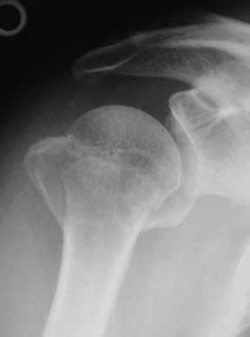

Question 21:

A 65-year-old active female presents to the emergency department after a mechanical fall. She complains of severe right groin pain and inability to bear weight. A representative radiograph of her injury is shown below. Assuming the image demonstrates a displaced (Garden IV) femoral neck fracture, which of the following is the most appropriate surgical intervention to maximize her functional outcome and minimize her lifetime revision rate?

Correct Answer: Total hip arthroplasty

Explanation:

For active, physiologically young older adults (typically 65-75 years old) with displaced femoral neck fractures, Total Hip Arthroplasty (THA) is the treatment of choice. Multiple randomized controlled trials have demonstrated that THA yields better long-term functional outcomes (e.g., higher Harris Hip Scores) and lower reoperation rates compared to hemiarthroplasty. Hemiarthroplasty (unipolar or bipolar) is generally reserved for lower-demand, older, or cognitively impaired patients. Internal fixation with cannulated screws for a Garden IV fracture in this age group carries an unacceptably high risk of nonunion and avascular necrosis.